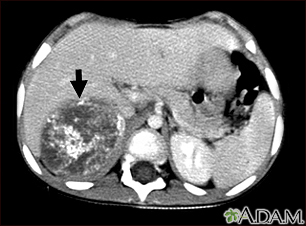

Tomografía computarizada de neuroblastoma en el hígado